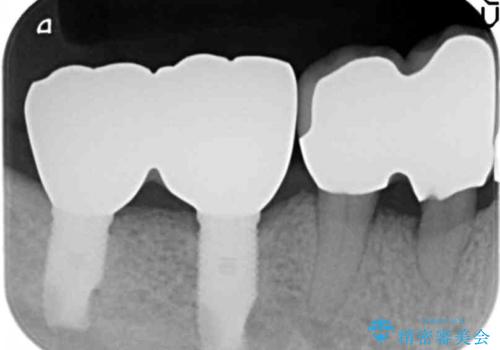

精査したところ、全顎的な重度の歯周病により右下の大臼歯2本(右下76)が欠損していました。

禁煙指導と歯周病治療後、右下の大臼歯2本(右下76)のインプラント治療を行いました。

インプラントの種類:スプラインツイスト(HAコーティング)

固定様式:スクリュー固定

クラウンの種類:ベレッツァクラウン